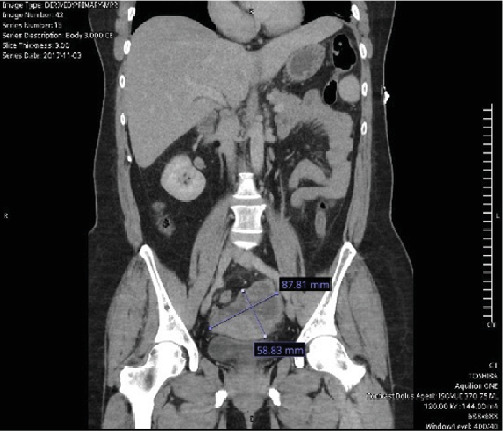

Background: Advanced stages of ovarian clear cell carcinoma have poorer prognoses than many other ovarian cancers. When standard treatments are ineffective, alternative options are needed. Case: A 56-year-old woman was diagnosed with ovarian clear cell carcinoma and treated with surgical management as well as carboplatin and paclitaxel. At recurrence, her disease progressed despite multiple chemotherapy regimens. A durable response was achieved first with alpelisib, chosen based on genomic testing. When progression occurred on this agent, a partial disease response was achieved with the combination of nivolumab and ipilimumab. Conclusion: The use of targeted therapies as well as the combination of nivolumab and ipilimumab is a promising option in advanced and recurrent cases of ovarian clear cell carcinoma.